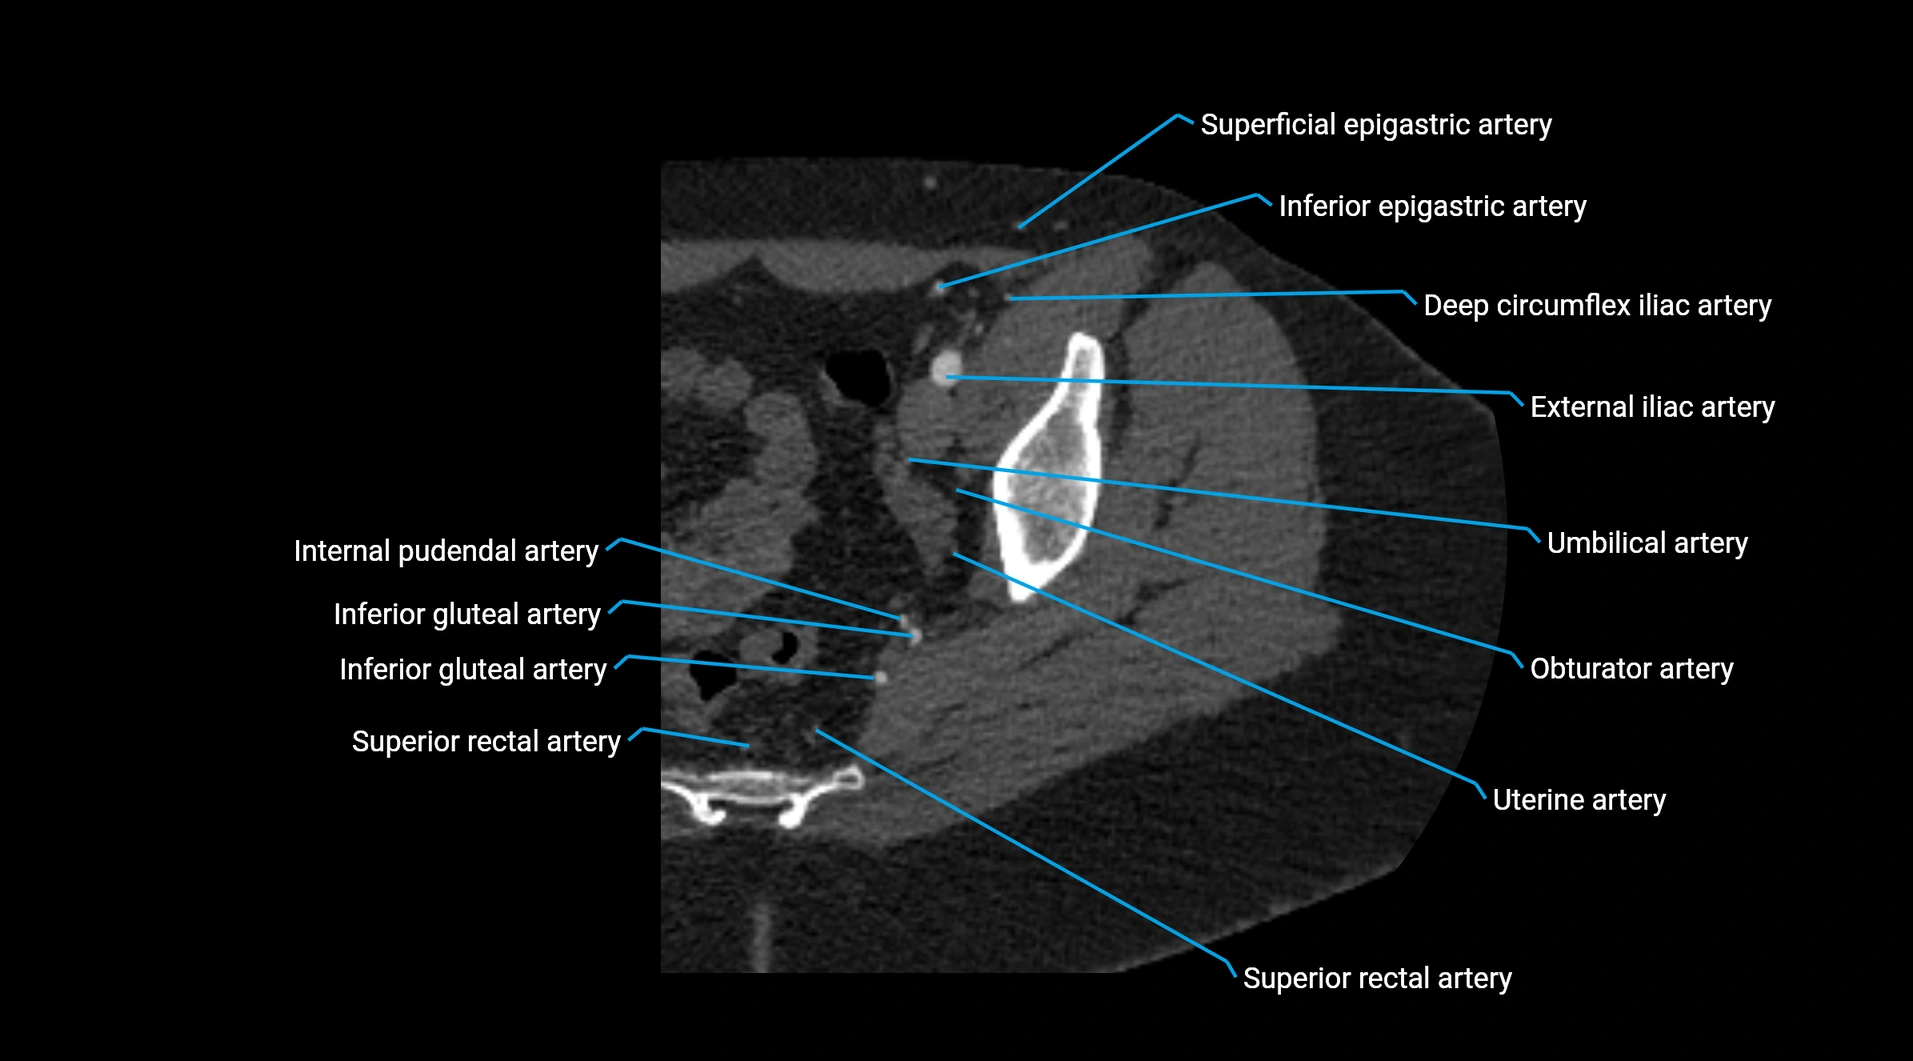

CT images

image